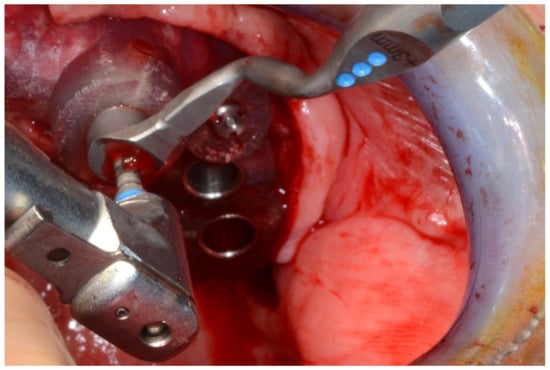

Figure 22.

Maxillary surgical drilling guides temporarily supported and fixed with mini-screws.

Figure 23.

Mandibular surgical drilling guides temporarily supported and fixed with mini-screws.